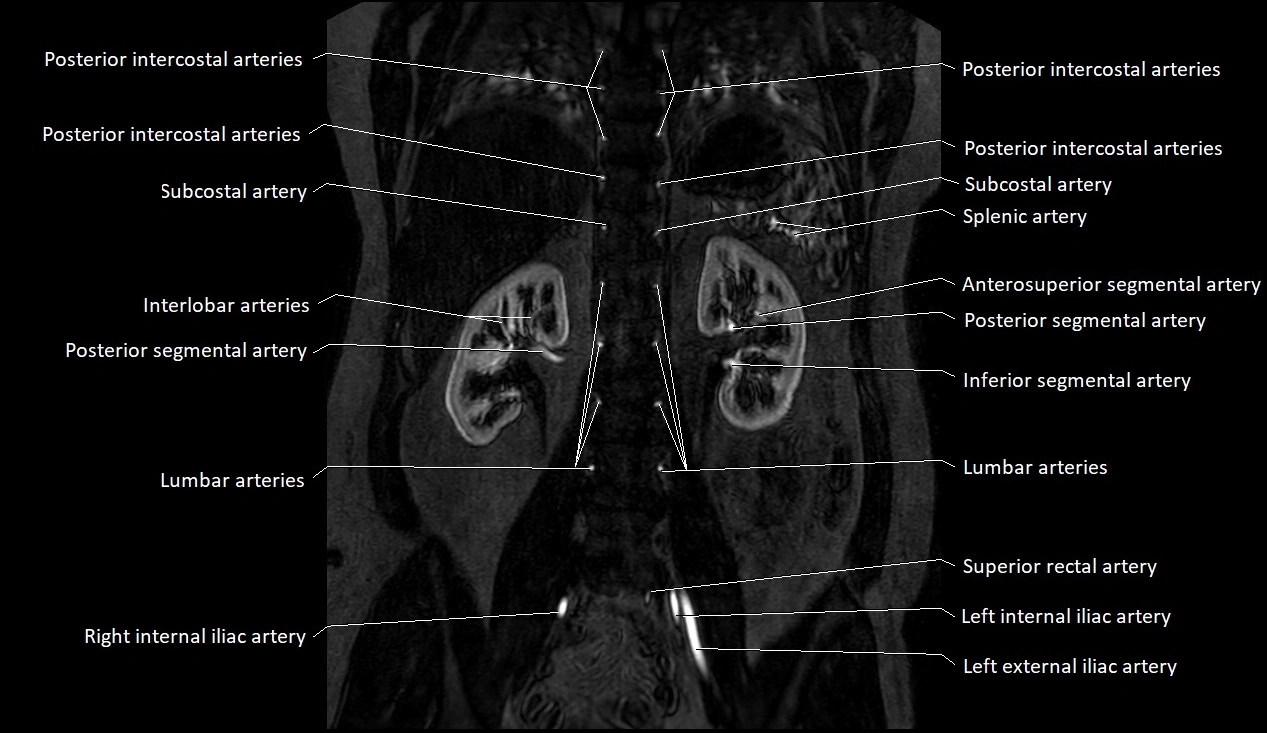

CT images

image